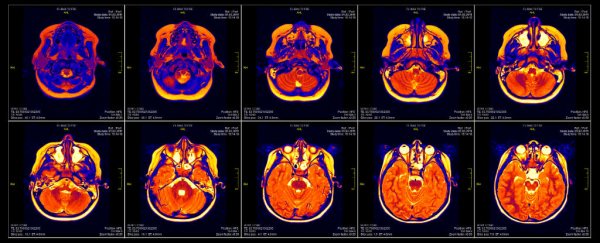

- fMRI (imagen por resonancia magnética funcional): detecta el flujo sanguíneo asociado con el aumento de actividad neuronal. Tiene una gran profundidad y resolución espacial (analiza cualquier zona del cerebro) pero baja resolución temporal, no detectando actividades que duren menos de unos pocos segundos. Detecta la activación de cualquier circuito cerebral y, por tanto, su relación con las respuestas emocionales, la involucración o el recuerdo. Es el método más invasivo y caro.

En un estudio clásico, a los participantes se les daba a beber de dos vasos con Coca-Cola y Pepsi mientras se les sometía a fMRI. Cuando los juicios se basaban puramente en información sensorial (con las marcas eliminadas) la actividad en una parte del circuito cerebral de evaluación predecía las preferencias de los participantes. Pero cuando se añadía el conocimiento de la marca, la de Coca-Cola (no la de Pepsi) sesgaba las preferencias y se asociaba con un aumento de actividad en partes del circuito de la memoria, incluyendo el hipocampo. Éste y otros estudios que siguieron proporcionaron la evidencia de que las acciones del marketing producen efectos sistemáticos e interpretables en el cerebro.